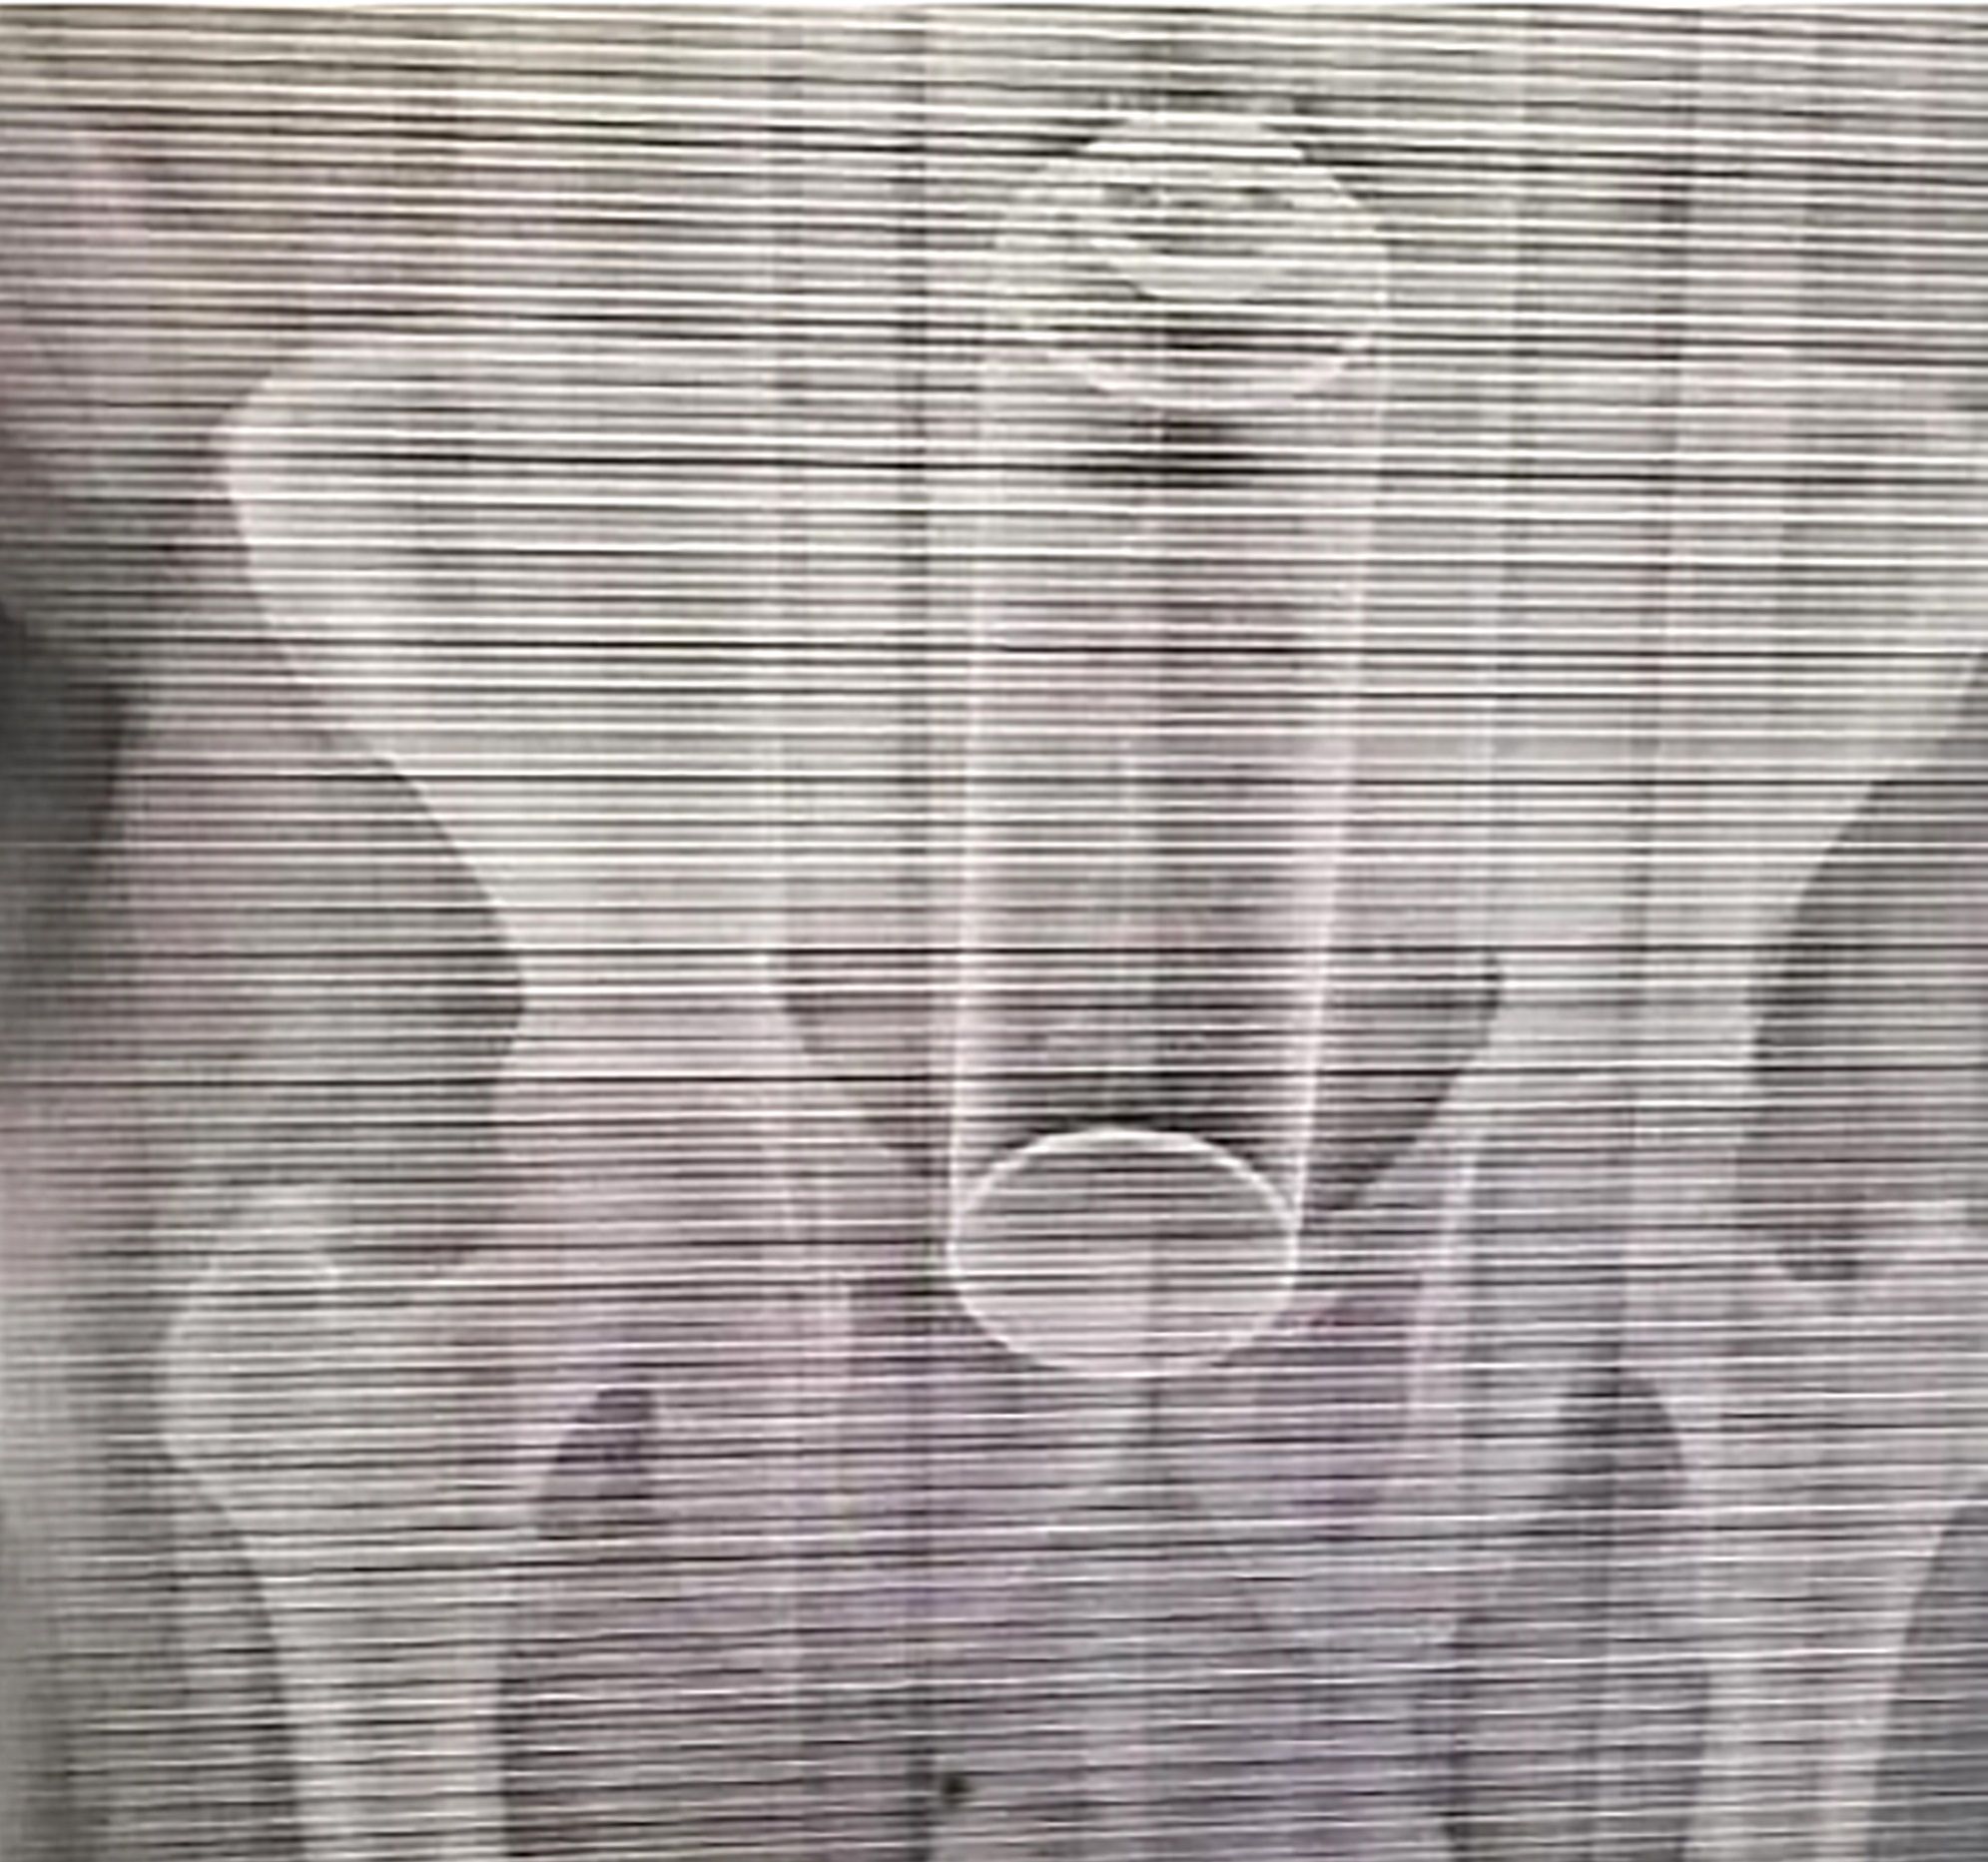

El médico puede palpar el objeto haciendo un tacto rectal con un dedo enguantado. Puede ser necesario realizar una exploración abdominal, una sigmoidoscopia (ver Endoscopia) y una radiografía para asegurarse de que la pared del intestino grueso no ha sido perforada.

Un hombre fue sometido a una intervención quirúrgica luego de que se le quedara atascado un desodorante de ambientes en el ano mientras tenía relaciones sexuales con su pareja.

El sujeto de 40 años ingresó al Hospital Moscoso Puello en República Dominicana y fue intervenido durante más de dos horas. Su mujer reveló que le introdujo el desodorante en el ano mientras tenían sexo.